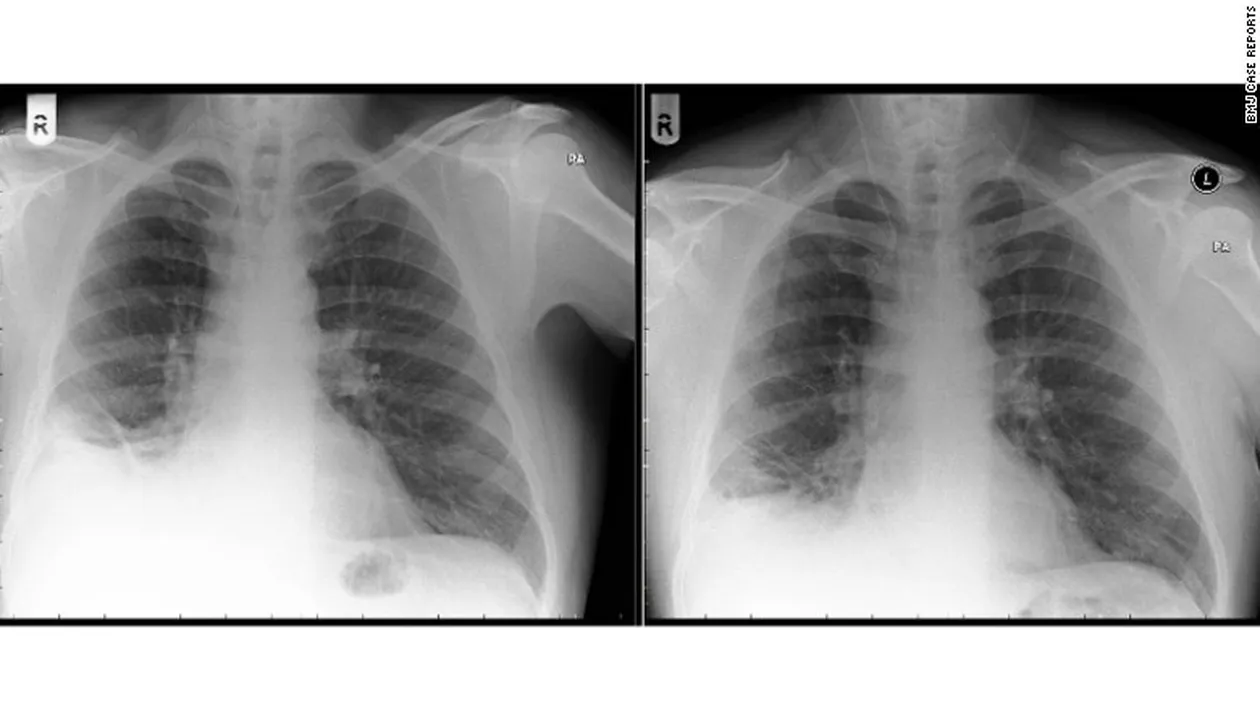

Un barbat in varsta de 50 de ani s-a prezentat la doctor cu dureri in piept si o tuse care nu-i mai dadea pace.

Problemele medicale ale pacientului au debutat pe cand avea 46 de ani. Doctorii care l-au consultat au crezut ca e un fel de cancer la plamani si ca trebuie operat.

In momentul in care l-au deschis, au ramas muti de uimire cand in locul unei formatiuni canceroase au descoperit o…

Se pare ca barbatul a inghitit-o inca din 1974. In acel an, cu ocazia aniversarii varstei de 7 ani, barbatul a primit cadou un…